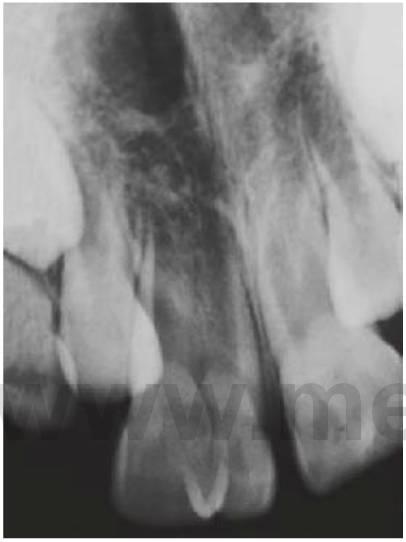

Dens invaginatus

Los incisivos laterales maxilares pueden presentar una invaginación (consecuencia del desarrollo) de la fosa cingular que presenta con frecuencia tan sólo una fina barrera de tejido duro que separa la cavidad oral y la pulpa. Suele producirse una necrosis pulpar poco después de la erupción del diente afectado y puede ocasionar un absceso o una celulitis en la fosa canina. Esta anomalía puede aparecer en otros dientes, como los incisivos centrales y caninos superiores (figs. 9 19,9.20).

Tratamiento

- Si ha erupcionado de forma reciente, se puede prevenir mediante el sellado de las fisuras de la superficie palatina.

- Si hay caries, colocar una resina de composite tras un grabado ácido.

- Si el diente es asintomático y la morfología del conducto radicular resulta favorable, se puede llevar a cabo el tratamiento endodóncico.

- Si la anatomía interna es compleja y el conducto radicular no resulta accesible, en caso de infección se procederá a la extracción del diente. Se debe analizar de forma exhaustiva la presencia de esta anomalía durante la planificación del tratamiento ortodóncico.